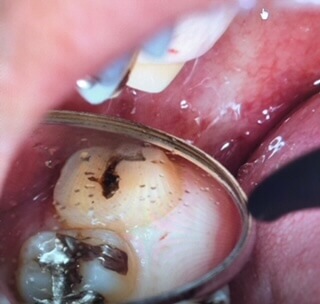

悪い歯を抜いた直後です。術前に歯肉に炎症があり、そこは脆弱なため抜歯時に裂開してしまいました。

縫合糸と強い接着剤を用いて移植歯を固定しています。

術後、2週間です。このタイミングで根管治療(根の神経の治療)を行っていきます。裂開していた歯肉は綺麗に治癒しています。